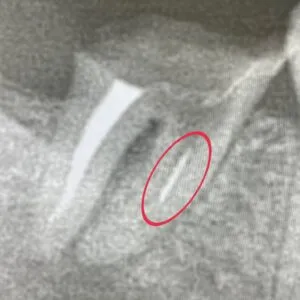

赤◯部分の破折ファイルは、マイクロスコープを使って取り除いたあとに、根管治療を行いました。

『破折ファイル』

破折ファイルとは、神経の治療中にファイル(根管内を清掃するための器具)が折れてしまい、根管内に取り残されてしまったファイルのことです。

パノラマを撮影すると、破折ファイルが残っていることがあります。

破折ファイルが残っていると、洗浄や消毒、最終的に入れるお薬をしっかりと入れることができません。